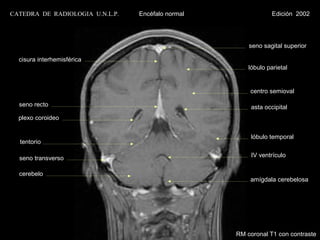

CATEDRA DE RADIOLOGIA U.N.L.P.   Encéfalo normal                Edición 2002

seno sagital superior

cisura interhemisférica

lóbulo parietal

centro semioval

seno recto                                            asta occipital

plexo coroideo

lóbulo temporal

tentorio

seno transverso                                       IV ventrículo

cerebelo

amígdala cerebelosa

RM coronal T1 con contraste